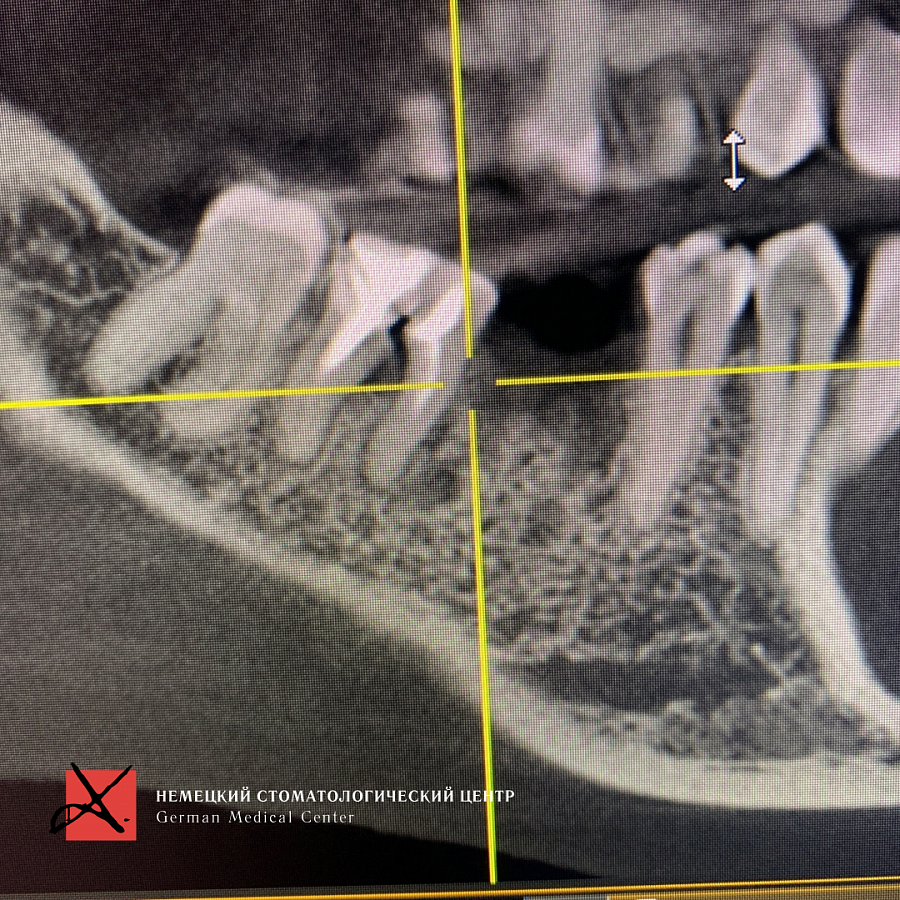

Пациентка обратилась с жалобой на перелом зуба, который ощутила при накусывании.

Провели имплантацию при помощи хирургического шаблона, который позволяет максимально точно спроектировать и спозиционировать положение имплантата для будущей функциональной нагрузки, грамотного распределения давления на имплантаты, а также здоровья зубного импланта. Операция прошла успешно.